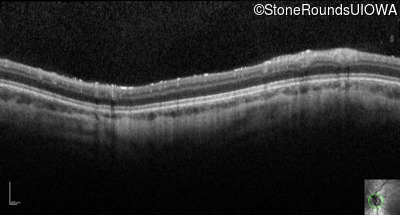

Optical Coherence Tomography - Right - 10/160 sc

Exemplar / OCT Stack